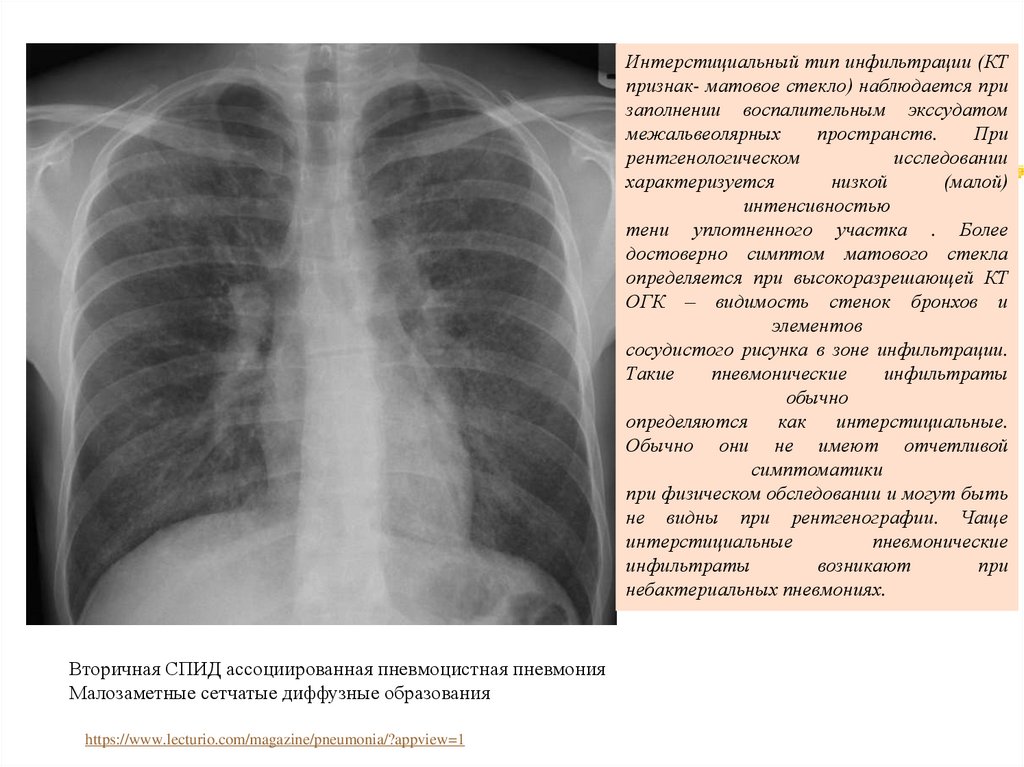

Интерстициальный тип инфильтрации (КТ

признак- матовое стекло) наблюдается при

заполнении воспалительным экссудатом

межальвеолярных

пространств.

При

рентгенологическом

исследовании

характеризуется

низкой

(малой)

интенсивностью

тени уплотненного участка . Более

достоверно симптом матового стекла

определяется при высокоразрешающей КТ

ОГК – видимость стенок бронхов и

элементов

сосудистого рисунка в зоне инфильтрации.

Такие

пневмонические

инфильтраты

обычно

определяются как интерстициальные.

Обычно они не имеют отчетливой

симптоматики

при физическом обследовании и могут быть

не видны при рентгенографии. Чаще

интерстициальные

возникают

небактериальных пневмониях.

Вторичная СПИД ассоциированная пневмоцистная пневмония

Малозаметные сетчатые диффузные образования

https://www.lecturio.com/magazine/pneumonia/?appview=1